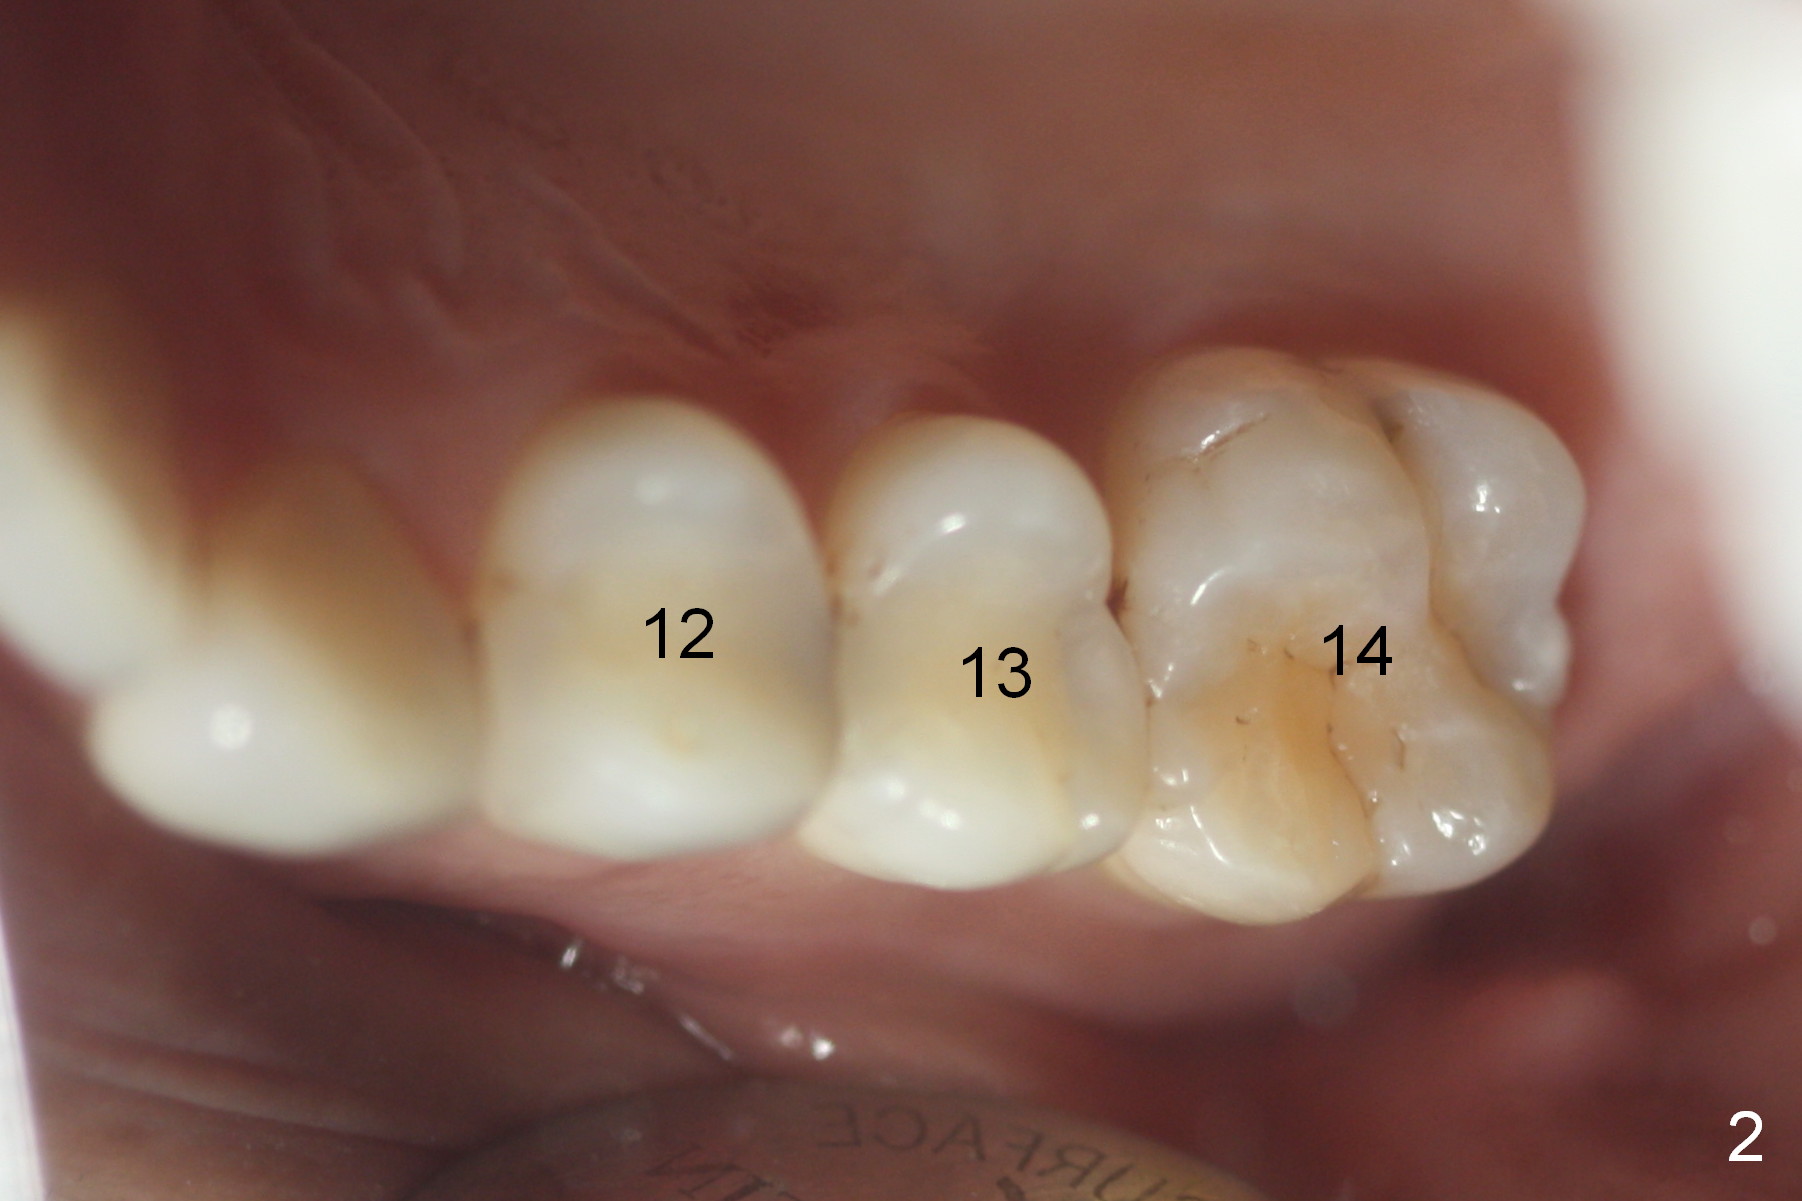

Ms. Li, a 34-year-old lady, had the upper right fixed partial denture made by an unlicensed dentist in California 10 years ago (Fig.1: #3-5). The gingival margin palatal to the retainers is erythematous (Fig.1 arrows). The patient's chief complaint is gum bleeding. The retainer at #3 is over-contoured buccopalatally (Fig.1, as compared to #14 in Fig.2), while the one at #5 is over-contoured buccopalatally and mesiodistally (compare to #12 in Fig.2). Panoramic X-ray (Fig.3), bitewing (Fig.4) and periapical film (Fig.5) all confirm that the bridge is over-contoured and that the retainers #3 and 5 have open margin (Fig.4 arrowheads). To improve oral hygiene and save the abutment teeth #3 and 5, it is in the patient's best interest to remove the bridge, place an implant at #4 and fabricate single-unit crowns at #3 and 5. Three to four months later, pyogenic granuloma develops between #4 and 5 (Fig.6 *) with generalized gingival erythema apically. The pontic at #4 and the retainer at #5 are to be removed first. An implant will be placed at #4 (Fig.7) with conjoined provisional at #4 and 5. The initial depth of osteotomy is 13 mm with Sinus Master Kit.